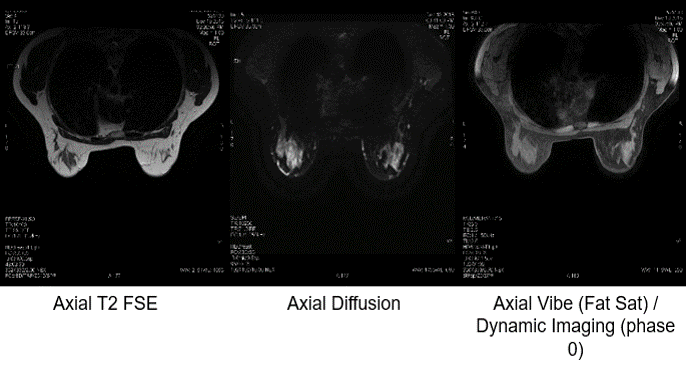

This set of images of the breasts is also T2 weighted. Again, we have a T2 FSE, and Axial Diffusion and a variation of the Axial T2 Fat Sat. If you recall in module 5, we learned that all vendors have proprietary pulse sequence names that are unique to them but describe pulse sequences used by all vendors. Here, the fat suppression is slightly more pronounced than on the previous slide of the skull.

In the first image, we see that the breasts are composed mostly of fat. Fat is relatively bright on the T2. In the Fat Suppressed sequence in the last image, the fat is now dark, because it has been suppressed. Again, all three images display T2 contrast, but in different ways.